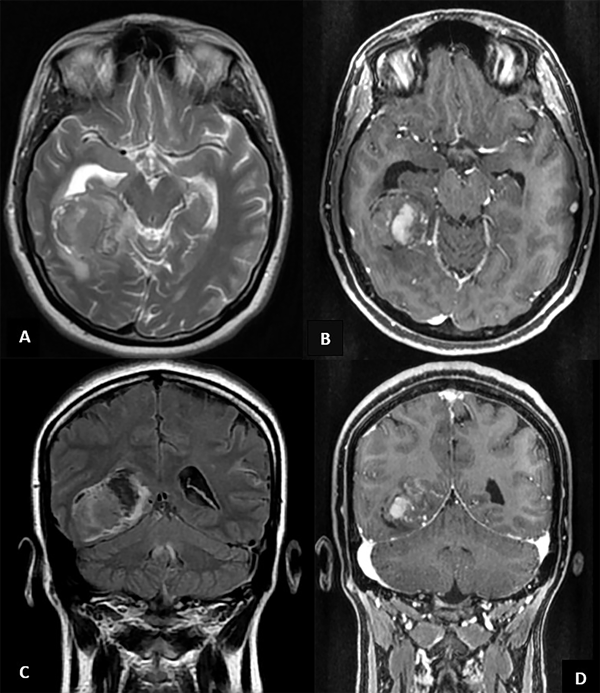

La paciente regresa por guardia 48 horas después de la primera consulta por persistencia de los síntomas. Se realiza inicialmente una tomografía computada (TC), donde se observa una lesión ocupante de espacio de tamaño moderado, con signos de probable hemorragia intralesional y restos de sangre en cuerno temporal derecho. Se da aviso al servicio de neurocirugía debido a los hallazgos por imágenes y se efectúa una resonancia magnética (RM) (Figura 1).

Figura 1. A) Corte axial en T2, se observa una masa temporal paraventricular derecha, irregular, con efecto de masa moderado. B) Corte axial en T1 con contraste. Obsérvese la captación heterogénea del gadolinio. C) Corte coronal en FLAIR. D) Corte coronal en T1 con gadolinio.